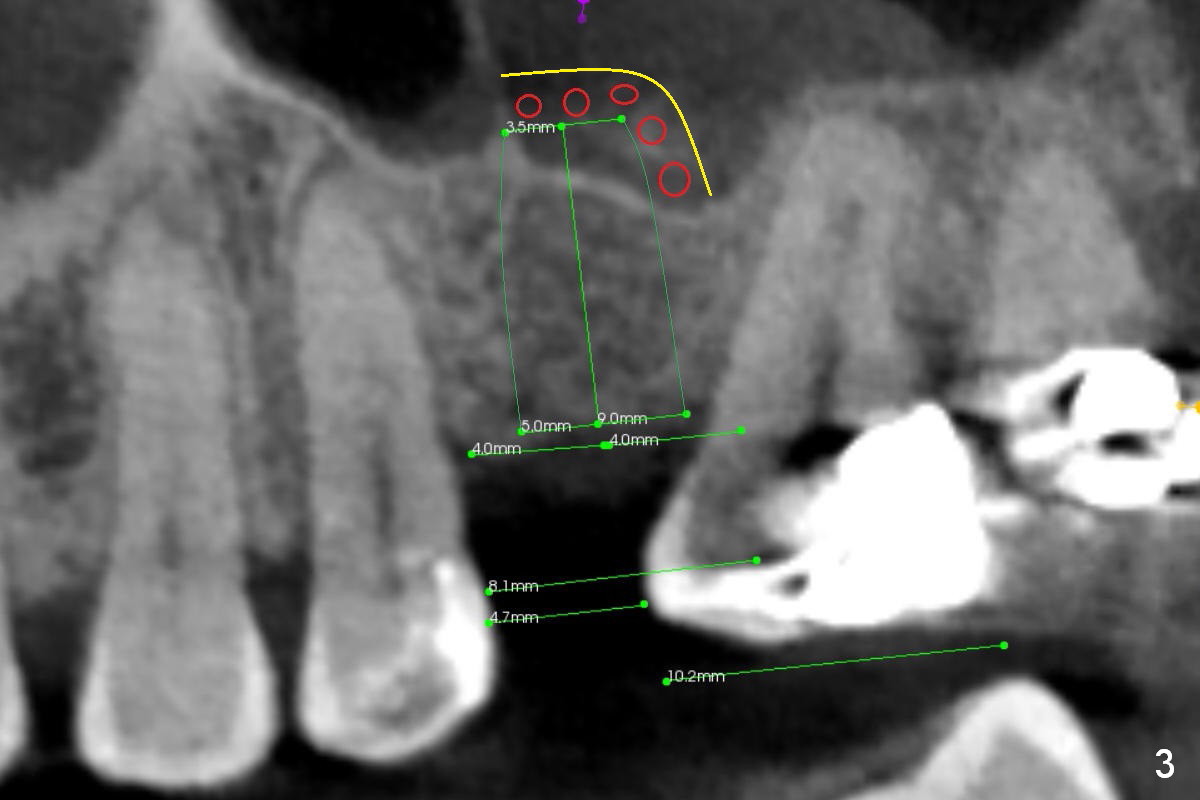

CT shows a residual root in the left maxillary sinus. In order not to re-infect the sinus, an implant at the site of #14 should not enter the sinus (Fig.2) or enters the sinus with bone graft (Fig.3,4 red circles) and more importantly PRF membrane (yellow).

Traditional segmental orthodontic treatment (open coil spring) is to be conducted to increase the mesiodistal width from 4.7 mm to 8 mm to place a 5 mm implant (Fig.2,3). Once the implant osteointegrates, it will be used an anchorage to further distalize the tooth #15.